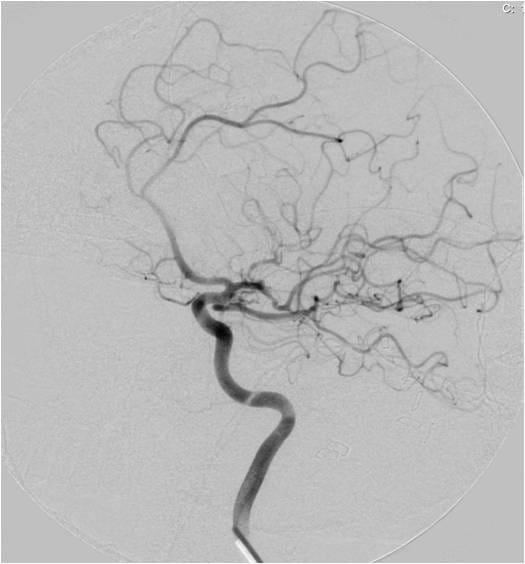

This video documents the surgical clipping of a giant middle cerebral artery aneurysm. The patient is a 56-year-old woman with a Grade I subarachnoid hemorrhage.

Supplemental photos also accompany the video below.